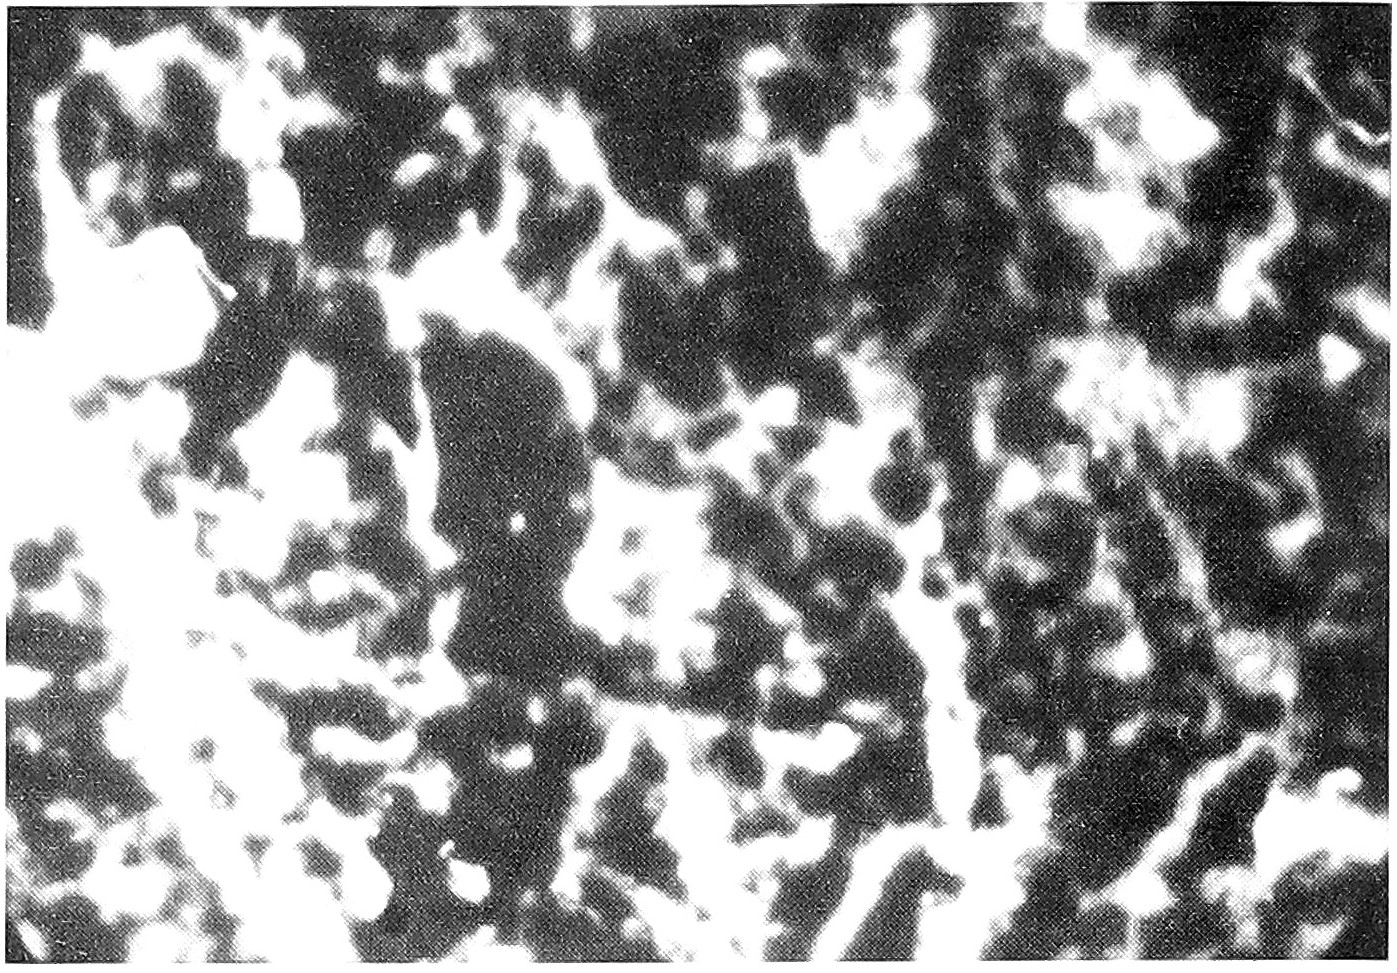

Из 29 перинатально погибших плодов и новорожденных было 7 (24,1%) с аномалиями развития. 3 из них погибли интранатально, 3 - сразу после родов и 1 - антенатально. Из 7 у трех были множественные пороки развития. У 1 - аномалия пупочного канатика, у 1 - волчья пасть и заячья губа, у 1 - врожденный порок сердца и у 1 аномалия развития почек. Все женщины, родившие детей с множественными пороками, перенесли ОРВИ до 5 нед. беременности. У всех трех в плаценте и органах плода выделен антиген гриппа A (H1N1). Мать ребенка, родившегося с волчьей пастью и заячьей губой, ОРВИ перенесла в 5 нед. и затем еще многократно при беременности. В плаценте и печени ребенка выделен антиген А (H1N1), в легких и мозге - A (H1N1) и PC. И в плаценте, и мозге ребенка с врожденным пороком сердца выделен антиген АД, а из печени АД + А (H1Nl) (pиc. 1,2, 3,4).

Рис. 3. Специфическое свечение антигена гриппа A(H2N2) в печени. Метод прямой флуоресценции, ув. 200.

Рис. 4. Специфическое свечение антигена гриппа A (H2N2) в мозге. Метод прямой иммунофлуоресценции, ув. 200.